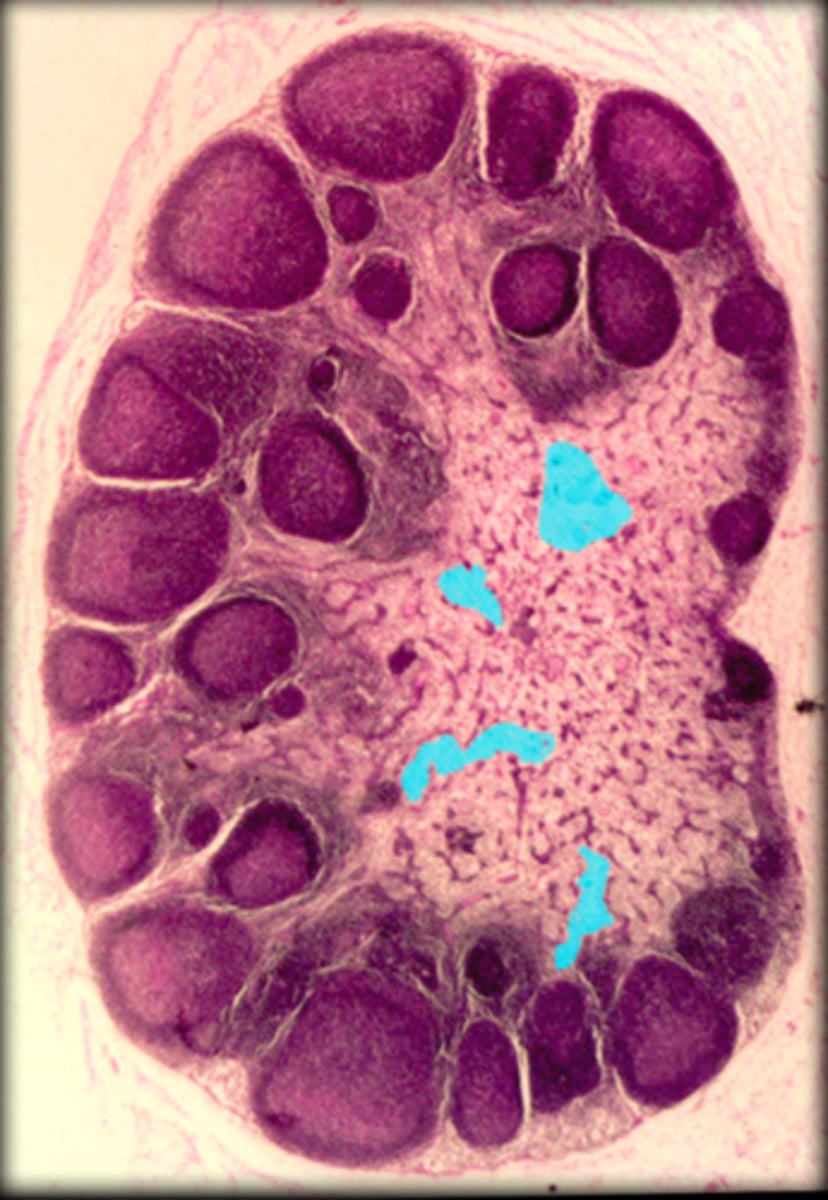

Lymph node

cortex

medulla

medullary cord

-There are some T-lymphocytes and macrophages are collected here.

medullary sinus

-This area is filled with lymph.